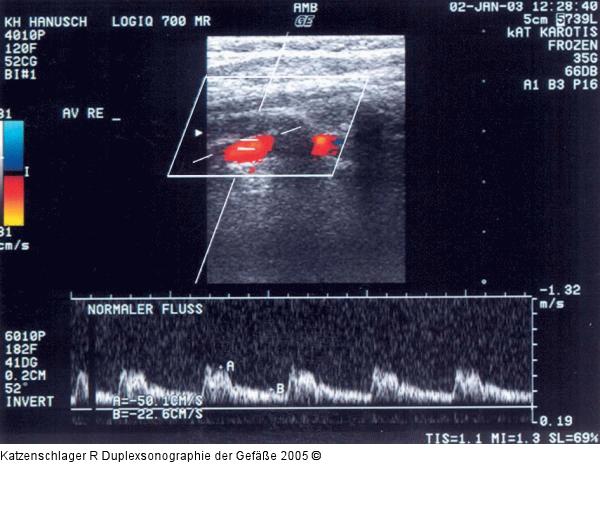

Abbildung 5: Duplexsonographie - A. vertebralis

Normalbefund der A. vertebralis |